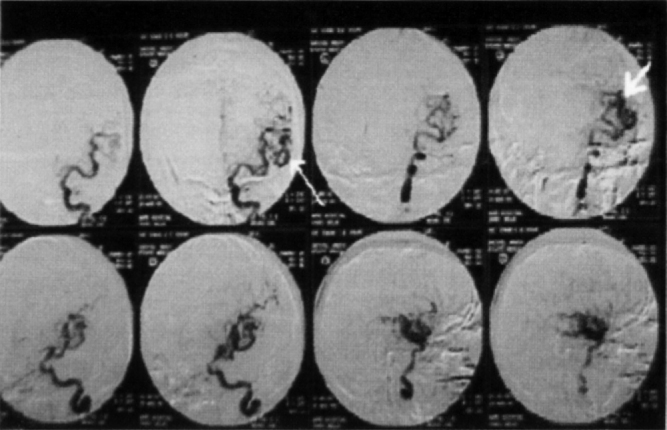

Individual was put on anti-cerebral oedema measures and anti-convulsant therapy. The AVM was large and located in the left fronto temporal region. The AVM was not amenable to surgery in view of the large size and eloquent location. Hence, a therapeutic embolization was planned via super selective DSA because of definite risk of intracranial haemorrhage in such a large AVM. Therapeutic embolization was planned in Sep 1999. Surprisingly, pre-embolic DSA revealed complete resolution of AVM (Fig 3).

Fig. 3.

DSA showing complete resolution of left fronto temporal AVM.